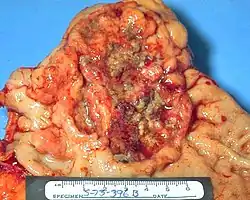

![]() Una úlcera estomacal que fue diagnosticada como cáncer en una biopsia y extirpada quirúrgicamente. | ||

El adenocarcinoma gástrico es un tumor epitelial maligno, originado en el epitelio glandular de la mucosa gástrica. Invade la pared gástrica, infiltrándose en las mucosas de los muscularis, la submucosa y por lo tanto en la lámina propia de los muscularis. Continúa su crecimiento invadiendo la capa muscular propia, la serosa y finalmente los órganos vecinos. Se define como cáncer gástrico incipiente o precoz a aquel que solo invade la mucosa o submucosa independientemente del compromiso ganglionar.[6]

Histológicamente, hay dos tipos importantes de adenocarcinomas gástricos (clasificación de Lauren):[7] tipo intestinal y tipo difuso. El adenocarcinoma tipo intestinal: las células del tumor describen las estructuras tubulares irregulares, abrigando la pluriestratificación, lúmenes múltiples, tejido conectivo reducido. A menudo, se junta la metaplasia intestinal en la mucosa vecina. Es asociado más a metaplasia y a un proceso de gastritis crónica. El adenocarcinoma tipo difuso: tiene su origen en células mucosas gástricas, no asociado a gastritis crónica y es mal diferenciado.